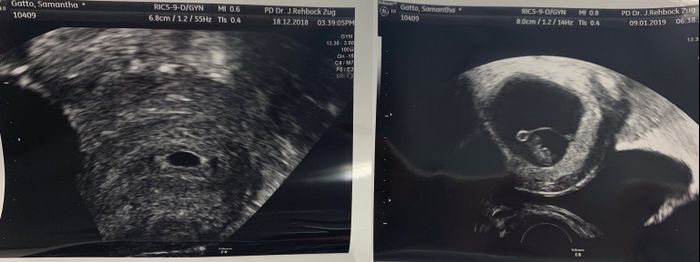

Da Samantha , Il 9 Gennaio 2019 alle 19:43

Buonasera a tutte! Ho scoperto il mio positivo da 2 giorni, sono a 3+4 e la mia dpp è il 9 agosto 2019. Ho visto che non c'è ancora un post per agosto 2019 ed ho pensato...